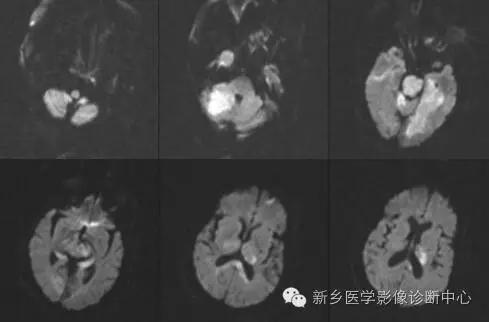

影像表现

影像表现:

脑部CT、MRI检查,显示累及基底动脉尖部5条血管供血区的2个以上梗死灶。常见部位依次为:丘脑、中脑、小脑、枕叶、颞叶等。

最大特征为双侧丘脑梗死,病灶位于丘脑中心部位,成蝶形、对称性分布。